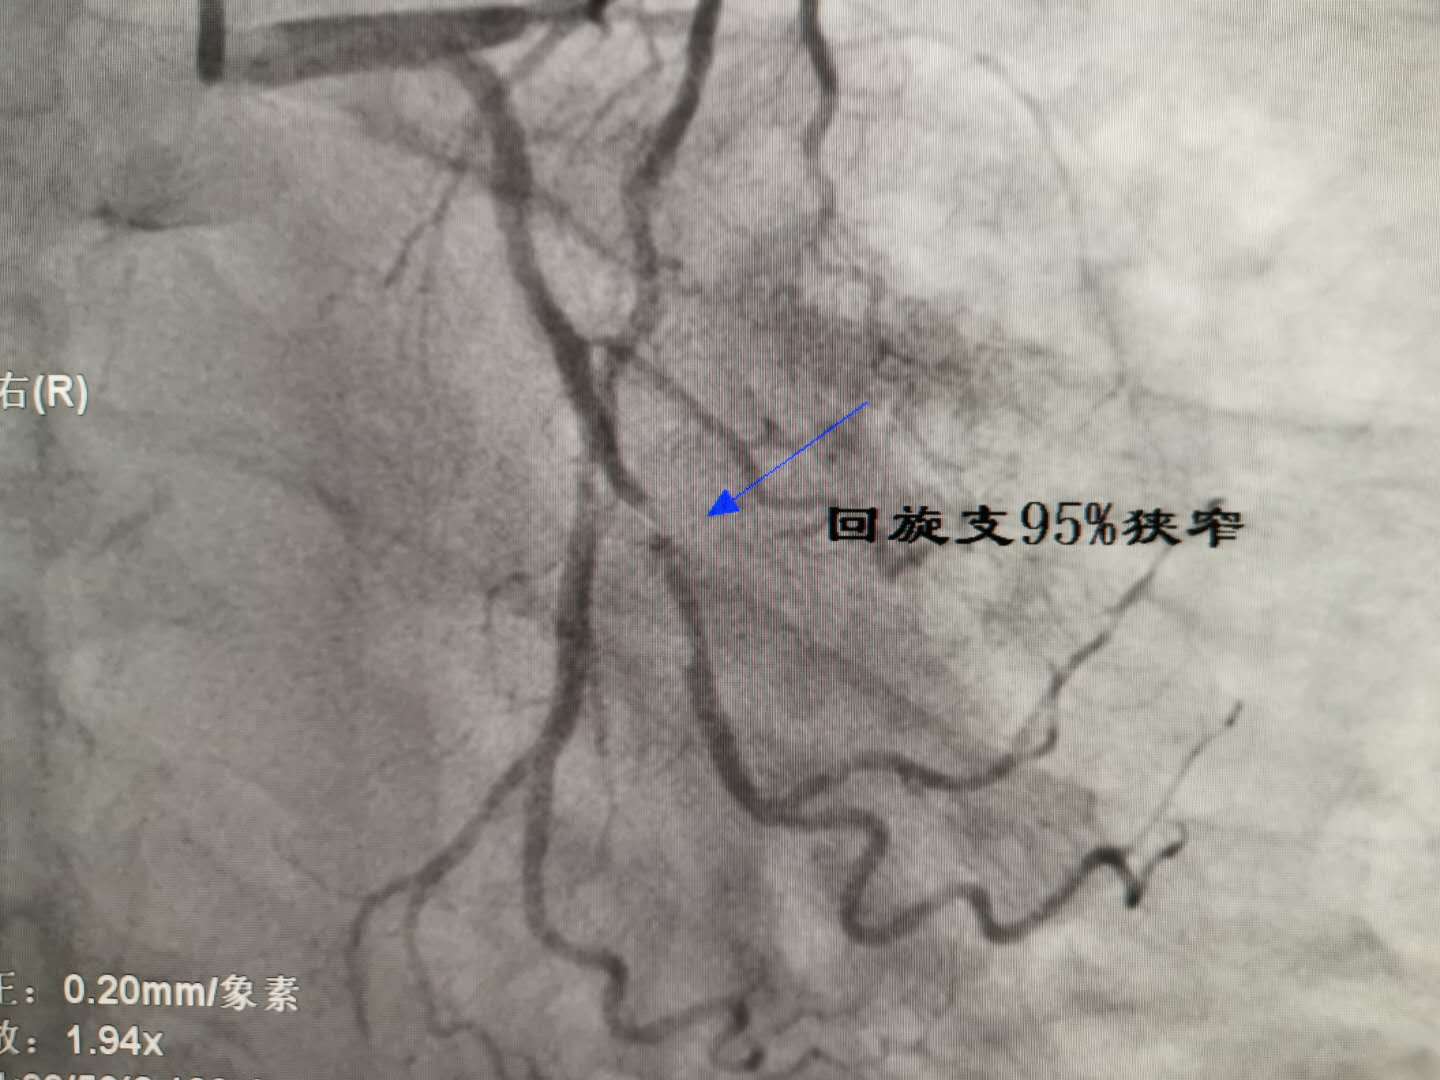

左主干重度狭窄 回旋支开口重度狭窄 - 丁香园论坛